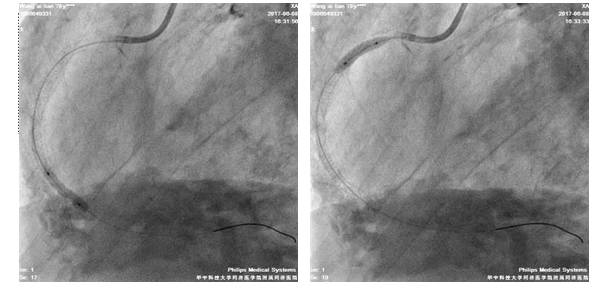

我院冠脉造影

LM严重钙化,体部散在斑块;LAD近段-中段弥漫性钙化伴狭窄,最重处约70%

LCX弥漫性钙化伴狭窄,最重处狭窄约90%

RCA开口处严重钙化,近中段弥漫性狭窄,中段最重狭窄达90%,狭窄最重处达90%,伴溃疡

6F JR4.0/GC

BMW/GW

2.5*20mmTazuna扩RCA中段8-16atm

3.0*33mm DES置入RCA中段

3.5*36mmDES置入RCA近段10-14atm,与前支架串联

3.5*15mm Hiryu 扩RCA8-20atm

术后造影